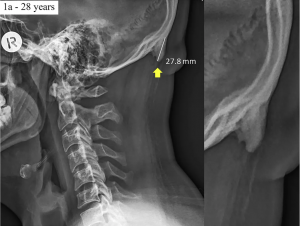

澳洲研究發現低頭族的另一項症狀:頭骨後長出「骨刺」(更新:研究爭議) 作者 Nana Ho|發布日期 2019 年 06 月 26 日 19:39 | 分類 會員專區 , 生物科技 , 醫療科技 | edit 科技為我們帶來許多便利,但不良的使用習慣同時也造成身體許多變化,最近澳洲研究人員發現當「低頭族」的另一項危害:長期低頭使用智慧手機之下,許多人都在頭骨後方有角狀骨骼生長,其中又以年輕族群的情況最明顯。 繼續閱讀..